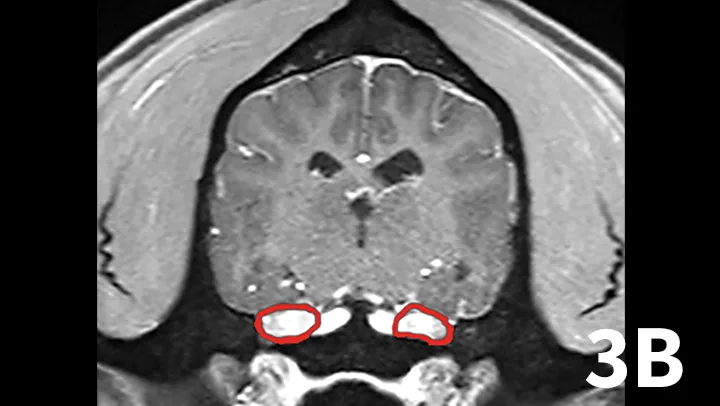

A range of infectious and noninfectious inflammatory diseases can affect peripheral nerve branches. The most frequently recognized inflammatory entity in dogs affecting peripheral branches of cranial nerves is trigeminal neuritis or idiopathic trigeminal neuropathy (ITN).5 Affected dogs typically have an acute onset of clinical signs secondary to bilateral motor branch dysfunction of the trigeminal nerves. This bilateral involvement of the trigeminal nerve results in inability to close the mouth (drop jaw), difficulty prehending food, and drooling.5 About 33% of dogs have sensory involvement of the trigeminal nerve, and <10% have Horner syndrome or facial nerve dysfunction.5 While the underlying pathogenesis of this disease is not known, it is believed to be noninfectious and inflammatory in origin.5 Other causes can be excluded via MRI and cerebrospinal fluid analysis. Reported MRI findings include bilateral, subtle enlargement of the trigeminal nerve with associated T2 hyperintensity (Figure 3).2 The reported mean time to recovery is 22 days with <10% of dogs taking >6 weeks to recover.5 No treatment beyond assisted feeding is recommended for ITN. It may be necessary to try several food consistencies to determine what will be easiest for a particular dog to prehend; rarely, feeding tubes may be necessary. Team members who handle dogs (or cats) with any acute neurologic disease process, especially involving the trigeminal nerves or lower motor neuron system, should wear gloves, as rabies is a differential diagnosis, especially in unvaccinated animals.

Transverse postcontrast T1WI at the level of the caudal thalamus from a normal dog (A) and a dog with trigeminal neuritis (B). The trigeminal nerves are outlined in each study in red. The dog with trigeminal neuritis has grossly enlarged trigeminal nerves without an overt, identifiable mass.